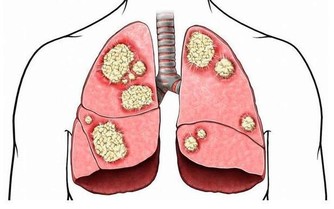

肝是「排毒工廠」,不養肝毒素堆成山

可見,肝臟對人體的重要性。肝不好會引起哪些症狀呢?下面我們一起來看看。

肝不凈會怎樣

1、肝「苦」毛病多,各器官養分不足

中醫講,百病之源,根在肝臟。

如果肝臟代謝不正常,人體所需養分得不到及時供應,各個器官無法正常工作。